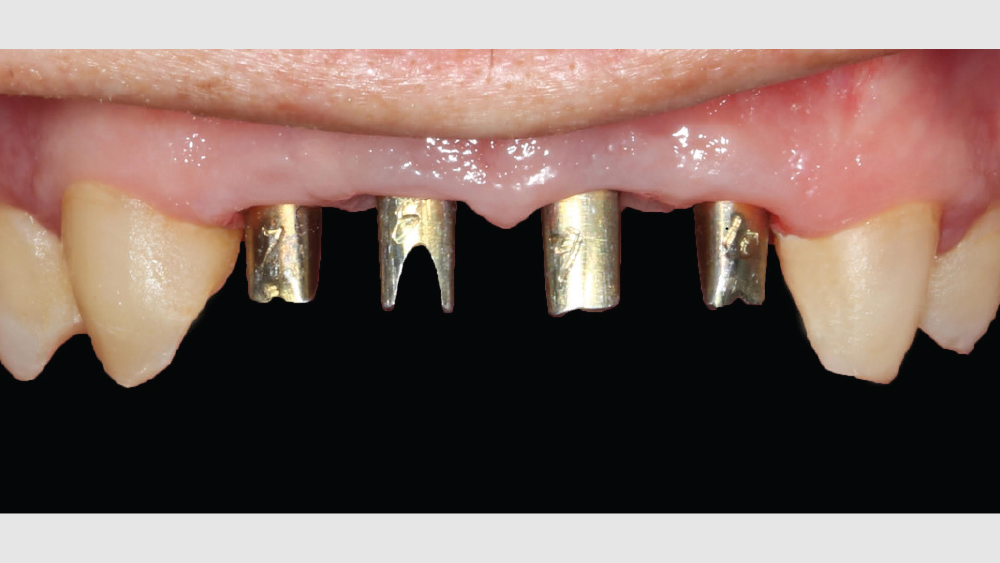

Digital treatment planning (DTP) with the team at Glidewell Laboratories allows me to ensure that implants are precisely placed, with full consideration given to the desired esthetics of the final restorations. But there was another unique element involved in planning the case described below: While it was esthetics that caused the patient to seek treatment, his career as a glass blower required his implants to be placed in functionally ideal positions. The potential complexity of these multiple requirements solidifed my decision to approach his case with implant positioning predetermined via DTP.

This patient came to me with four missing anterior teeth in positions #7–10. He had been missing these teeth for some time and was wearing a temporary denture to address the cosmetic issue this created. When he came to my practice, he was in a financial position to solve the problem permanently with implant restorations. Based upon the anterior space available and the fact that the patient’s surrounding tissue was in good health, I chose to move forward with Hahn™ Tapered Implants and BruxZir® Esthetic restorations.